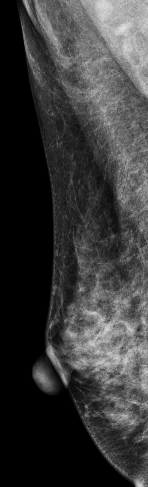

低能图像

常规检查:右乳偏外下象限见模糊类圆形结节影,CESM显示结节不均匀强化